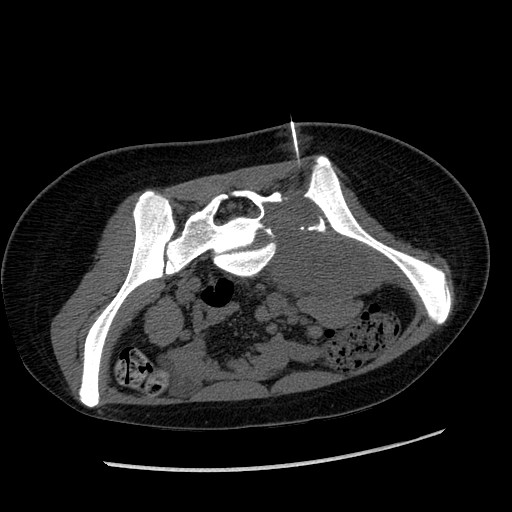

1.    The patient was a 3 year-old girl with the chief complain of left lower extremity that extended to the right side. Imaging demonstrated a large sacral mass that mainly affects her left side. These features are not sufficient for a definitive diagnosis but which of the following be the most likely diagnosis?  Answer

CT taken at the time

of the needle biopsy

(needle is shown here)

MRI FNA